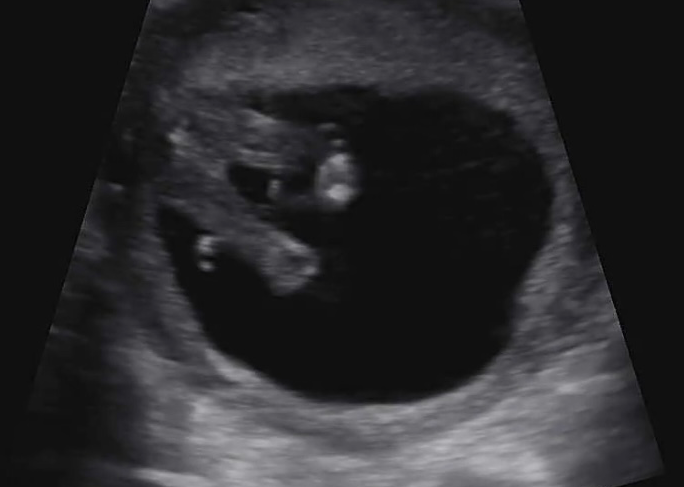

아직 난임병원과 분만병원을 병행으로 다니던 시기(난임병원 대기가 길어서 초음파 보러는 분만 병원을 종종 다녔다)였던지라 난임병원에서는 초음파 화질로 성별을 알 수 없었고 나름? 남자 아이라면 빨리 보인다기에 분만병원에서 조금 기대를 했었는데 예고 없이 불쑥 아기의 성별을 알려주셨다. 대체로 기형아 검사를 하면서 정밀 초음파를 받는 경우가 있는데 그때 성별을 고지해주는 경우가 많다. 근데 나는 이슈로... (이 이야기는 길어질 것 같으니 나중에 해보도록하겠다) 기본 초음파(투명대 길이 재는 것)와 피검사로 진행을 해서 성별을 아예 짐작도 못하는 상황이었는데.

의사 : 이정도면 거의 딸이에요 90% (가랑이 사이 사진을 보여주며) 사이에 아무것도 없죠?

나 : 오... (저렇게 매끈? 한데 아들이면 사기 당하는거다)

그렇게 의도치 않게? 빠르게 어쩌면 알고 있었을 성별을 알게 되고 걱정부터 앞선 딸맘... 여자아이는 섬세하다는데 이 험한 세상에서 닌자처럼 키워야겠다?!(아님)라는 마음을 먹었다.